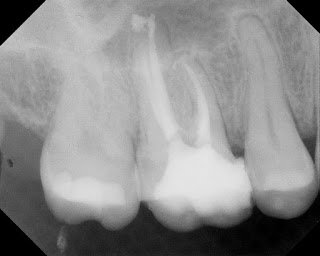

Upon accessing the pulp, we found a stained crack on the mesial and smaller crack on the distal. Pt was informed that these cracks would not be completely removed, and would affect the long term prognosis for the tooth. The patient, understanding that the prognosis is guarded, elected to preserve the tooth as long as possible by completing the RCT and placing a crown.

RCT was completed and returned to GP for coronal coverage.